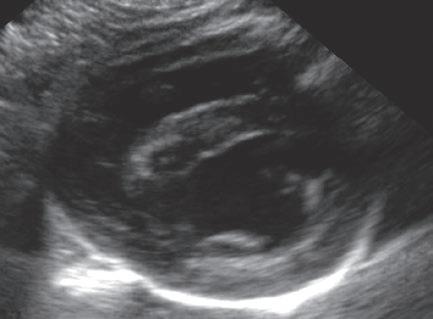

La responsabilidad de los artículos, reportajes, comunicados, etc. recae exclusivamente sobre sus autores. El editor sólo se responsabiliza de sus artículos o editoriales. La ciencia veterinaria está sometida a constantes cambios. Así pues es responsabilidad ineludible del veterinario clínico, basándose en su experiencia profesional, el correcto diagnóstico de los problemas y su tratamiento. Ni el editor, ni los autores asumen responsabilidad alguna por los daños y perjuicios, que pudieran generarse, cualquiera que sea su naturaleza, como consecuencia del uso de los datos e información contenidos en esta revista. De acuerdo con la normativa vigente en materia de protección de datos Grupo Asís Biomedia, SL., es responsable del tratamiento de sus datos personales con la finalidad de enviarle comunicaciones postales de nuestras revistas especializadas, así como otras comunicaciones comerciales o informativas relativas a nuestras actividades, publicaciones y servicios, o de terceros que puedan resultar de su interés en base a su consentimiento. Para ello, Grupo Asís podrá ceder sus datos a terceros proveedores de servicios de mensajería. Podrá revocar su consentimiento, así como ejercer sus derechos de acceso, rectificación, supresión, oposición, limitación y portabilidad enviando un correo electrónico a protecciondatos@grupoasis.com, o una comunicación escrita a Grupo Asís en Centro Empresarial El Trovador, planta 8, oficina I, Plaza Antonio Beltrán Martínez 1, 50002, Zaragoza (España), aportando fotocopia de su DNI o documento identificativo sustitutorio e identificándose como suscriptor de la revista. Asimismo, si considera que sus datos han sido tratados de forma inadecuada,